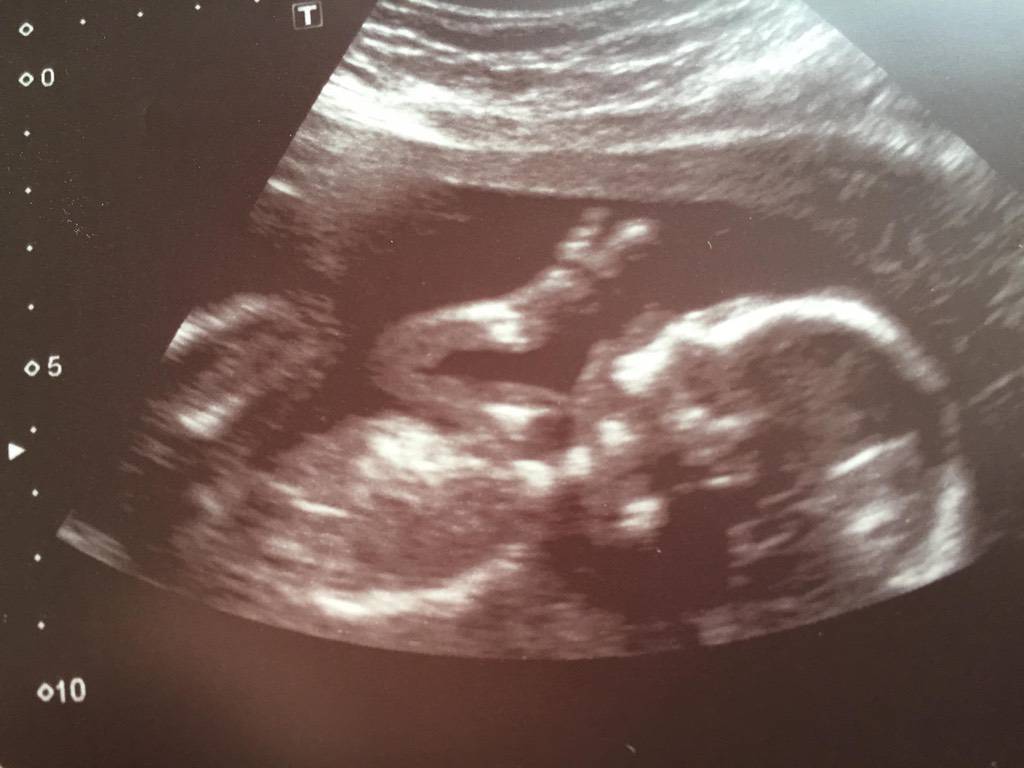

Hätt noch mehr Bilder aber ich glaub da erkennt man nichts..